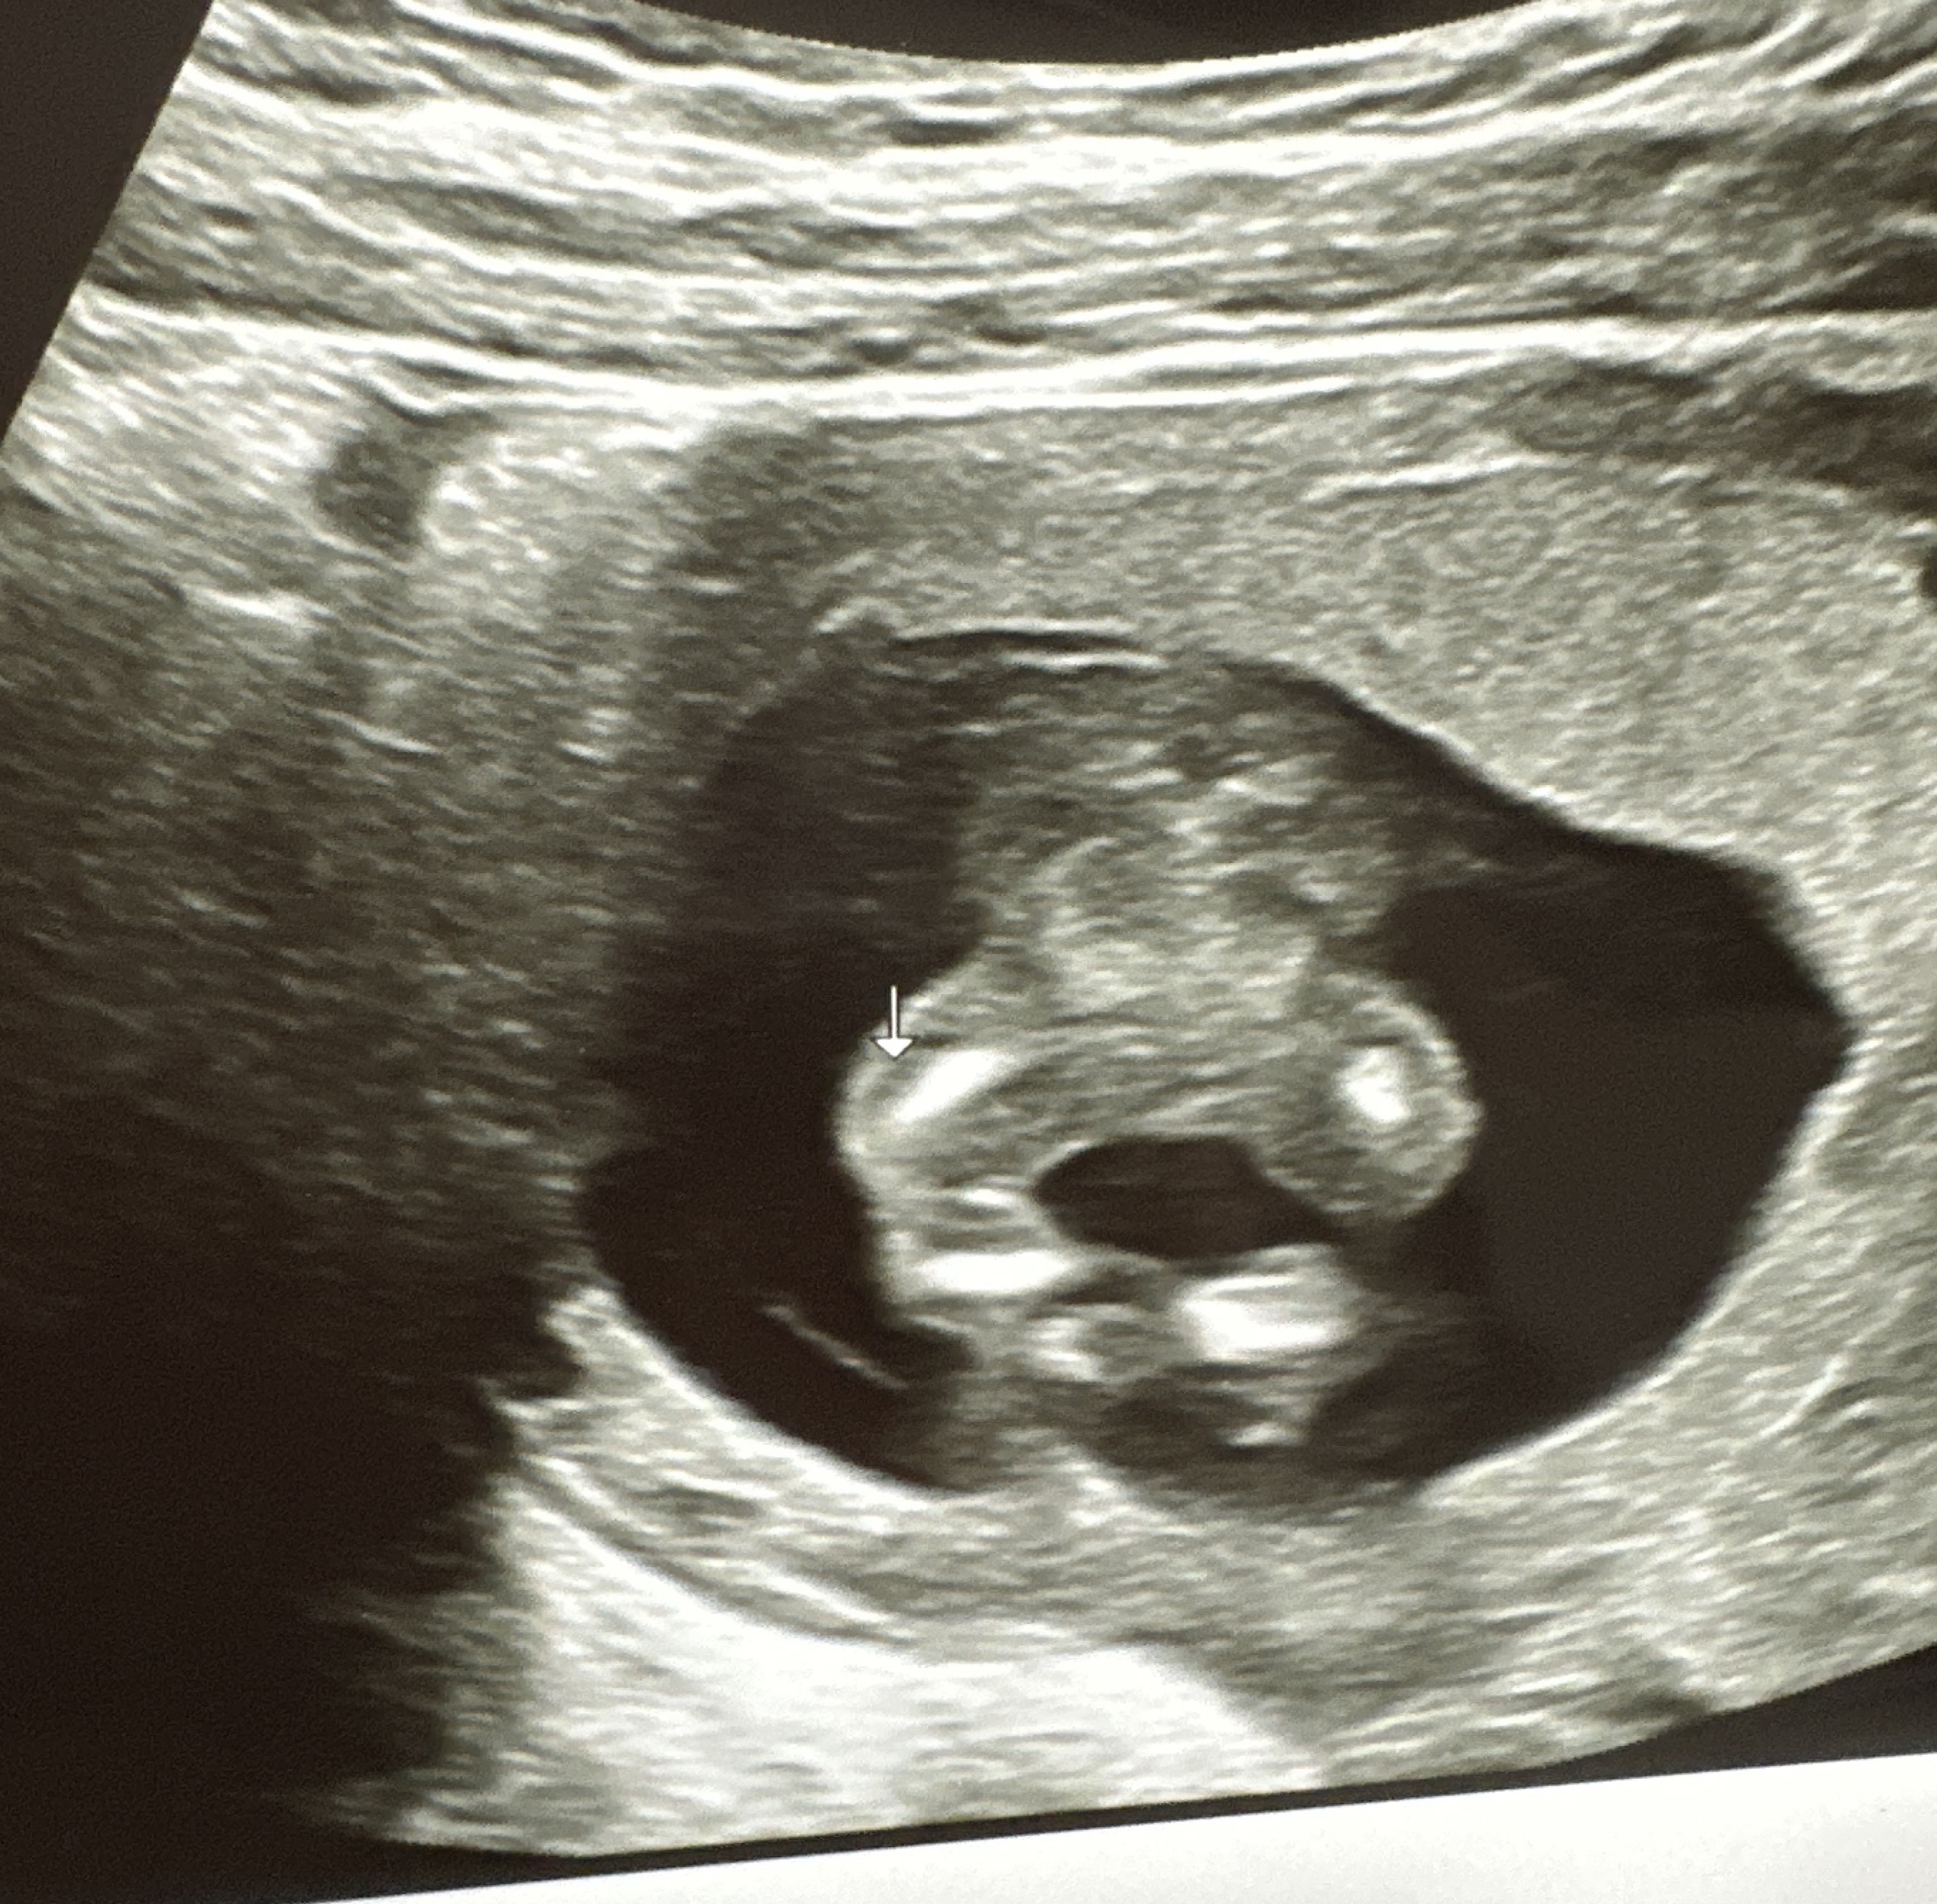

성별 봐주세요오!!!🫨

13주차고, 허벅지 보여주실 때 봤는데유..... 깨끗한 거 보니 딸인거겠죠......!?

딸같아요!